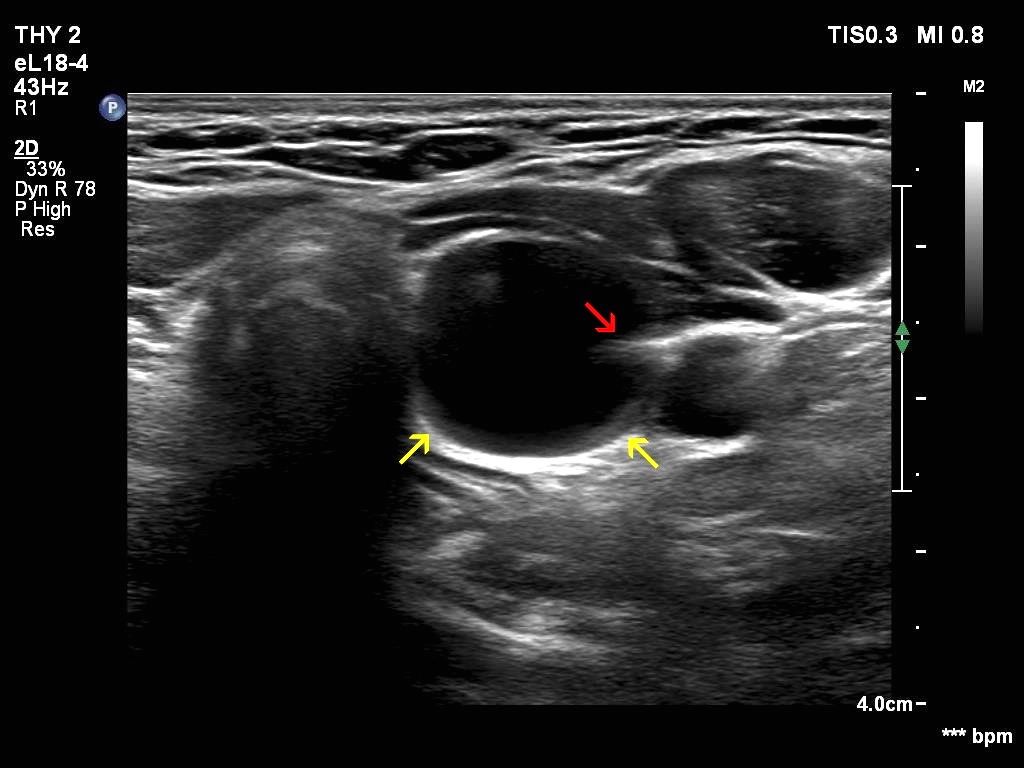

Transverse scan |

Longitudinal scan |

This is an almost completely cystic lesion, however it does not meet the criteria of a pure cyst. The wall thickening (yellow arrows) is ambiguous but there is a tiny solid-appearing area in the dorsal wall (red arrows). In systems which do not use the term 'almost completely cystic lesion', this nodule should be categorized as a peripheral-type cyst.